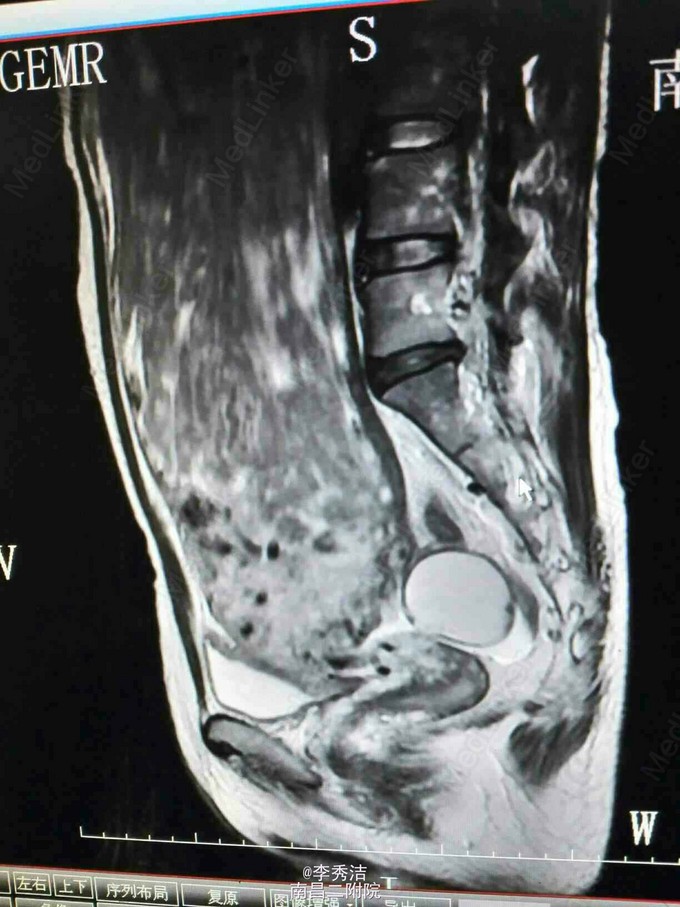

妇科检查:子宫孕9月大小,无压痛,活动。彩超示:子宫体积明显增大,内部呈蜂窝状考虑子宫肌瘤癌变,双侧附件区显示不清。腹部ct示:盆腹腔巨大肿块,子宫及双侧附件显示不清。

行剖腹探查术,术中见子宫血管显露,子宫底部触及一大小约35*30*12cm肌瘤样囊性包块,占据盆腹腔大部分,质软,表面光滑,充满手术野,包块与盆腔后壁肠系膜膜性粘连,右侧卵巢见一直径约5cm囊性包块,表面光滑。松解粘连后,行子宫肌瘤剔除术+右侧卵巢囊肿剔除术,剔除肌瘤16Kg。术中冰冻切片示:(子宫)初步考虑平滑肌瘤伴出血、变性。右侧卵巢良性囊性病变。诊断为1.子宫肌瘤变性,2.右侧卵巢囊肿。